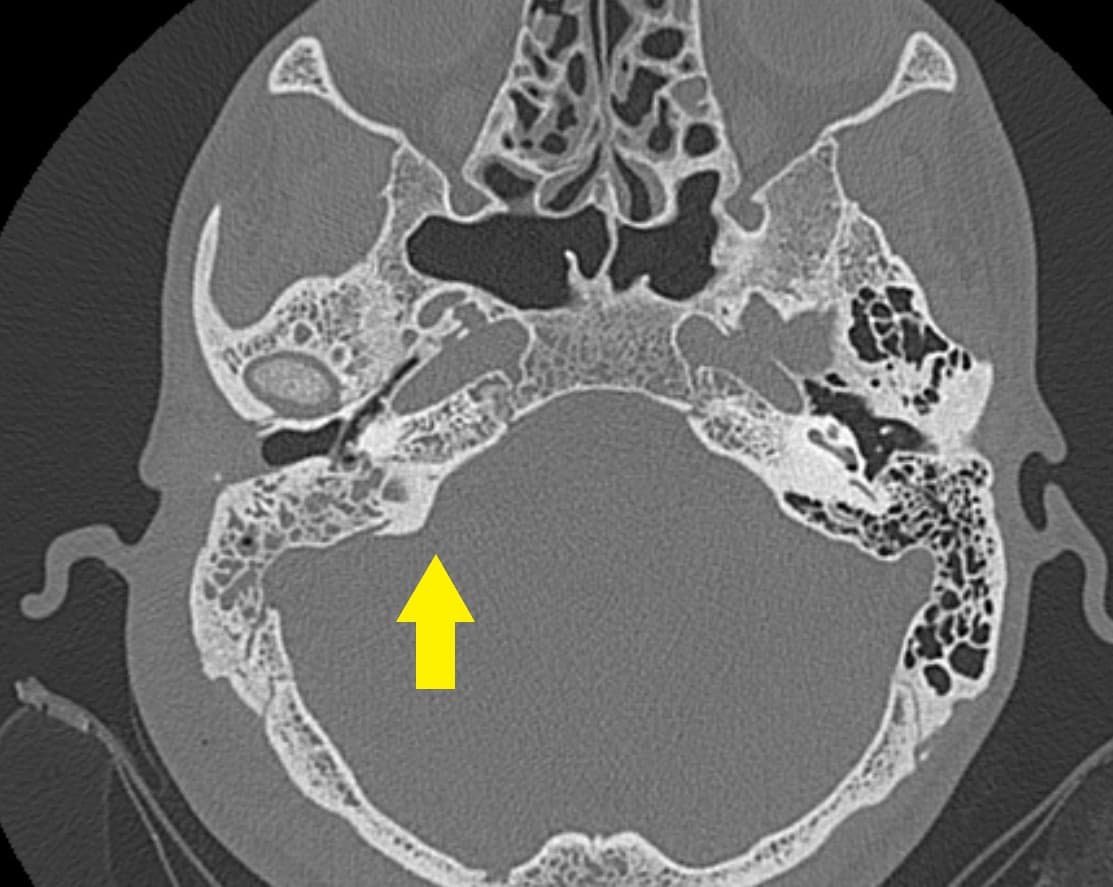

Phim chụp CT cho thấy hình ảnh của viêm xương chũm.

Bác sĩ sẽ dựa vào tiền sử viêm tai giữa, tiền sử chảy mủ tai và thăm khám lâm sàng. Ngoài ra các xét nghiệm và chẩn đoán hình ảnh giúp hỗ trợ chẩn đoán bệnh và các biến chứng của bệnh như:

– Chụp CT scan vùng thái dương